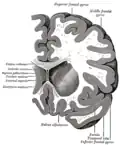

Section coronaire du cerveau immédiatement en face des ponts.